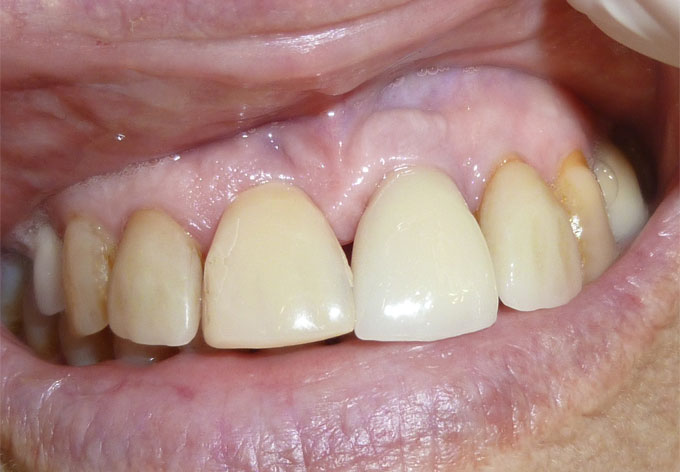

En estos casos han sido tratados con la filosofía de all-at-once, en la

misma sesión: